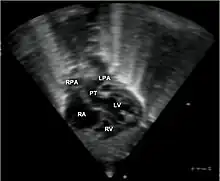

Additional images

Abbreviations: RA=right atrium, RV=right ventricle, LV=left ventricle, PT=pulmonary trunk, LPA and RPA=left and right pulmonary artery.